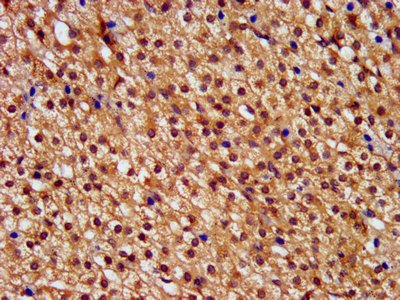

IHC image of CSB-PA868272LA01HU diluted at 1:400 and staining in paraffin-embedded human adrenal gland tissue performed on a Leica BondTM system. After dewaxing and hydration, antigen retrieval was mediated by high pressure in a citrate buffer (pH 6.0). Section was blocked with 10% normal goat serum 30min at RT. Then primary antibody (1% BSA) was incubated at 4°C overnight. The primary is detected by a biotinylated secondary antibody and visualized using an HRP conjugated SP system.